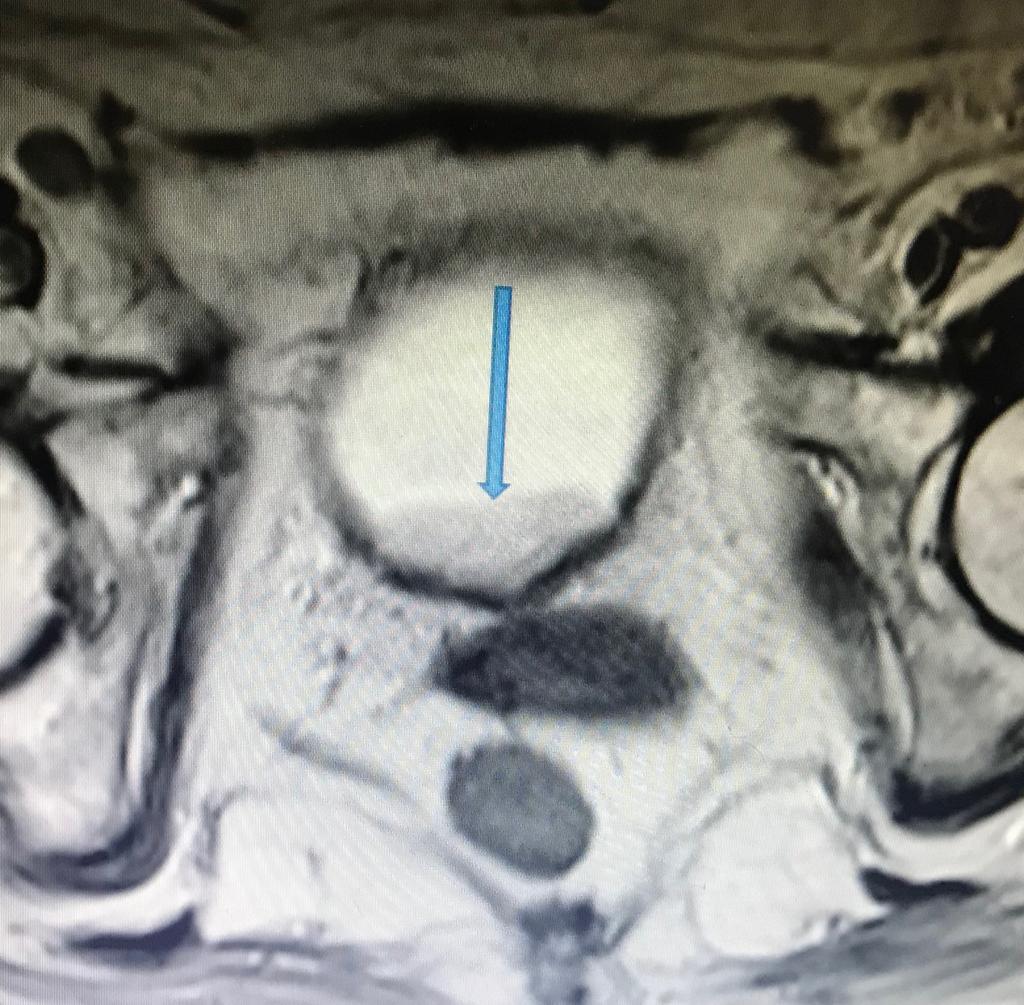

Caso RM de pelvis

Caso RM de pelvis RM Biparamétrica de vejiga. (Cáncer de vejiga) Femenina de 80 años, con prótesis en cadera derecha. Antecedente de IRC. No es posible realizar estudio de angiogénesis, por presentar TFG de 15ml/min y por consiguiente no administramos contraste...